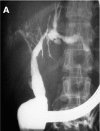

Patients: All nine patients had previously required long term treatment in an intensive care unit for septic shock: two patients with polytrauma, five with burn injury, and two with extensive surgery. They were admitted to our hospital because of cholangitis. Endoscopic retrograde cholangiography revealed severe intrahepatic stenoses in all patients and liver biopsies showed typical signs of sclerosing cholangitis. No patient had pre-existing liver disease.

Results: Mean follow up time was 35 months. In patients with major bile duct stenoses (3/9), 12 endoscopic dilations were performed in total. In one patient, concrements were extracted and intermittent stenting was necessary. To date, 4/9 patients have rapidly developed liver cirrhosis. During follow up, 5/9 patients died: two after fulminant cholangitis, one after liver failure, one due to liver transplantation associated problems, and one after cerebral ischaemia. One patient has been registered for transplantation and the remaining three patients show no acute signs of liver failure.